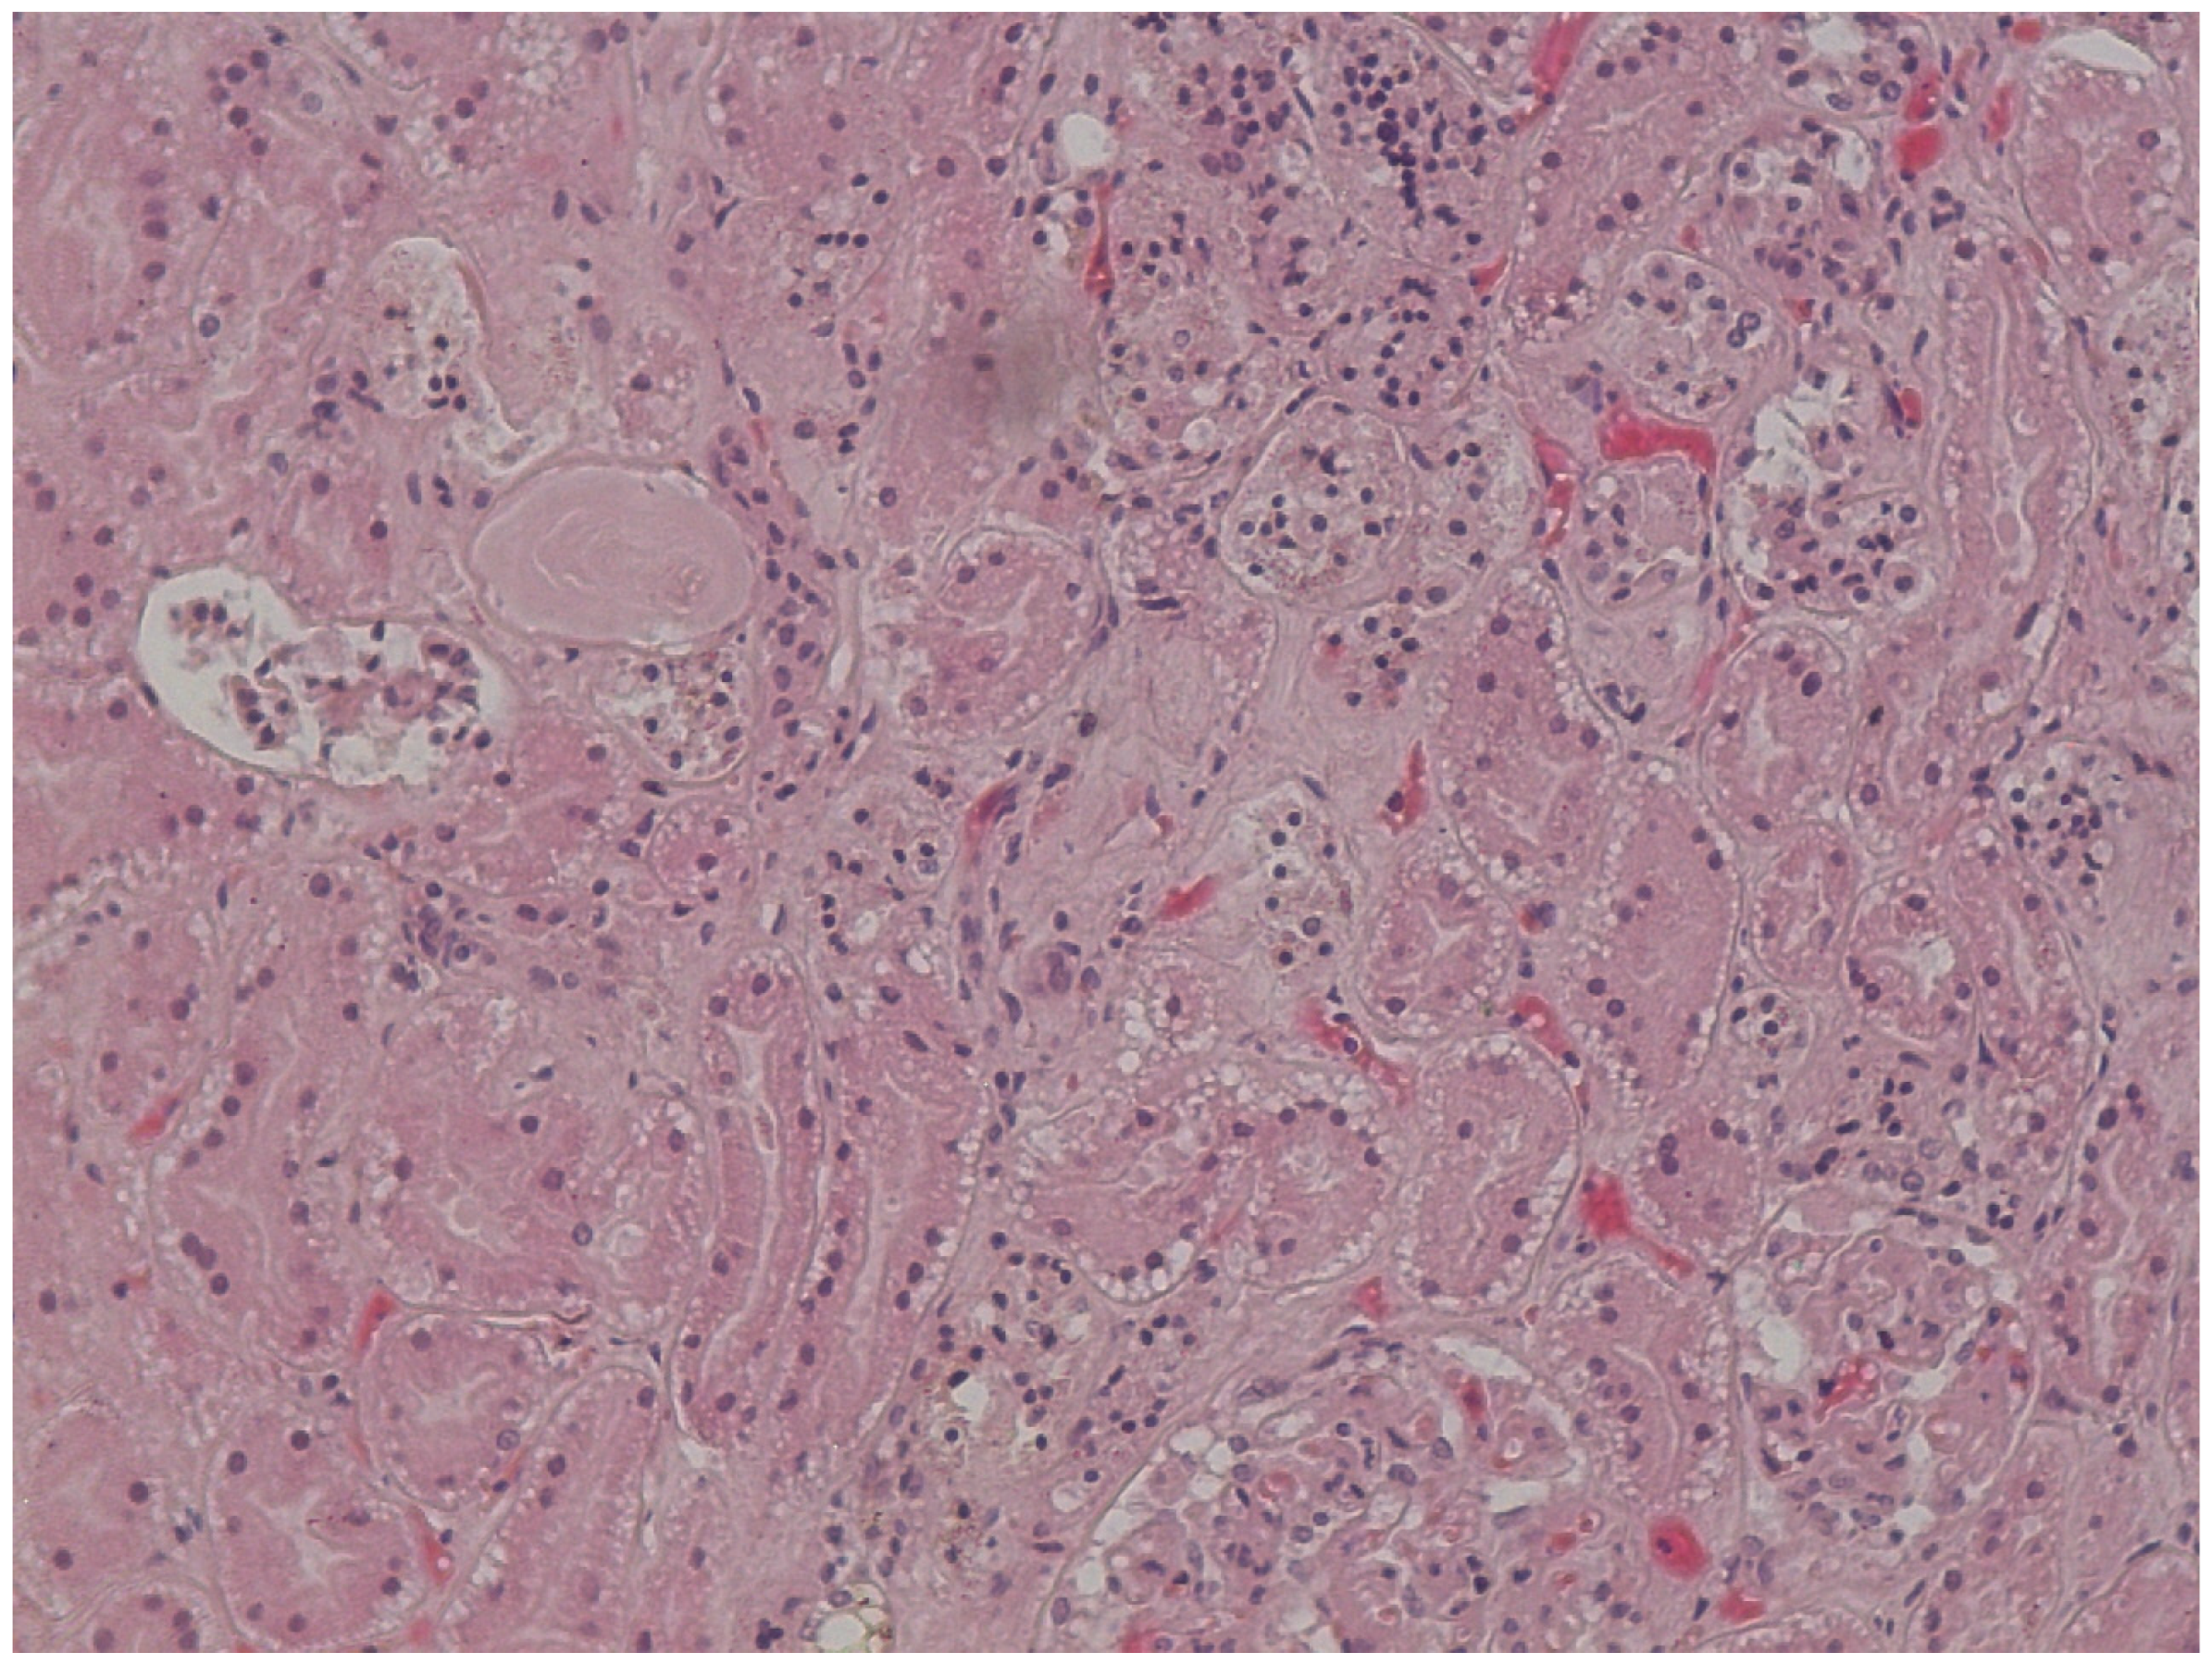

Microscopic observation of tissue sections stained with hematoxylin and eosin showed marked pulmonary congestion (Figure 7), micro- and macrovesicular hepatic steatosis (Figure 8), as well as vacuolization of the basal cells of renal tubules (Figure 9). Gastric wall showed edema and vascular congestion involving mucosa and submucosal layers and focal erosions of the mucosal surface consisting of necrotic foci delimitated by a dense lympho-histiocytic infiltrate (Figure 10). At the level of the skin discoloration (Figure 11), small hemorrhagic extravasations in the dermis were detected.

3.5. Subnuclear Vacuolization of Renal Tubular Epithelial Cells

The Armanni–Ebstein phenomenon consists in a lipidic vacuolization in the renal epithelium attributed to different pathological condition. Although the primary hypothesis was the attribution of these findings to diabetes [19], they may also be explained by hypoxia and altered fatty acid oxidative metabolism. This hypothesis was proposed by Preuss [20] because of the evidence of lipid vacuoles in 87% of the hypothermia cases. It appears to be a useful marker to confirm post-mortem diagnosis of fatal hypothermia, as well as the Wischnewski spots, but not to exclude it [21,22]. In our case, the diagnosis of hypothermia instead of diabetes was confirmed by the general practitioner of the deceased: he only suffered from hypertension, Alzheimer’s disease, and epilepsy.

Figure 9. Vacuolization of the basal cells of renal tubules.